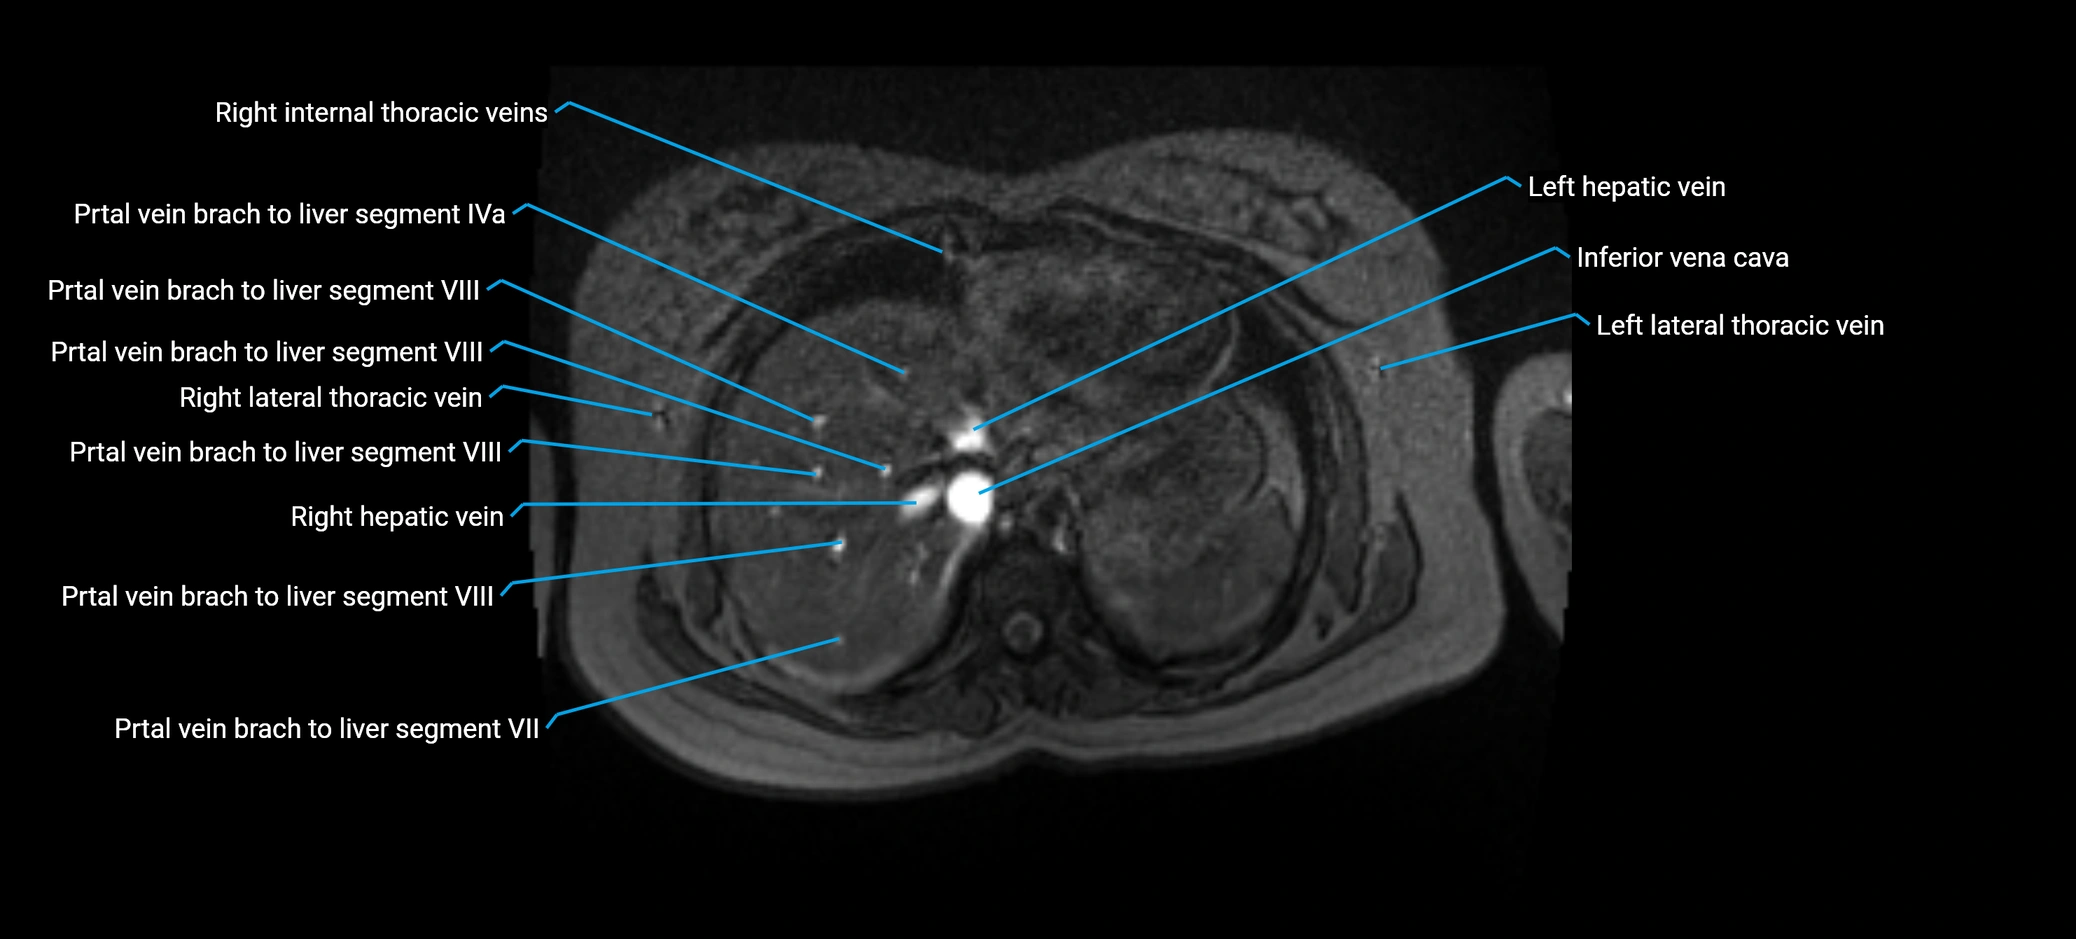

MRV TOF (Time-of-Flight MR Venography):

• Appears as a bright, high-signal vascular channel representing flowing blood

• Clearly shows branching pattern of right portal vein into anterior and posterior branches

• Best in coronal or axial reconstructions for segmental mapping

• No need for contrast, relies on flow-related enhancement

• Clearly delineates branching into segments V and VIII

• Best sequence for evaluating patency, caliber, and anatomic variants